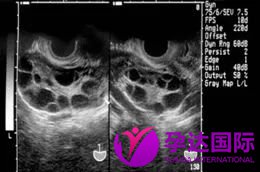

超声下的卵泡,只有募集更多的成熟卵泡才能提高试管婴儿成功率